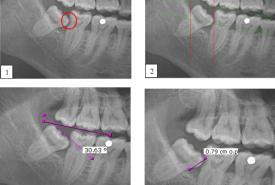

The Incidence of Mandibular Second Molar Distal Caries Associated with Impacted Mandibular Third Molar: A Retrospective Study and Management Guidelines

Original Article

21 Jul, 2025

Farah Hanan Fathihah Jaffar

Khairul Osman